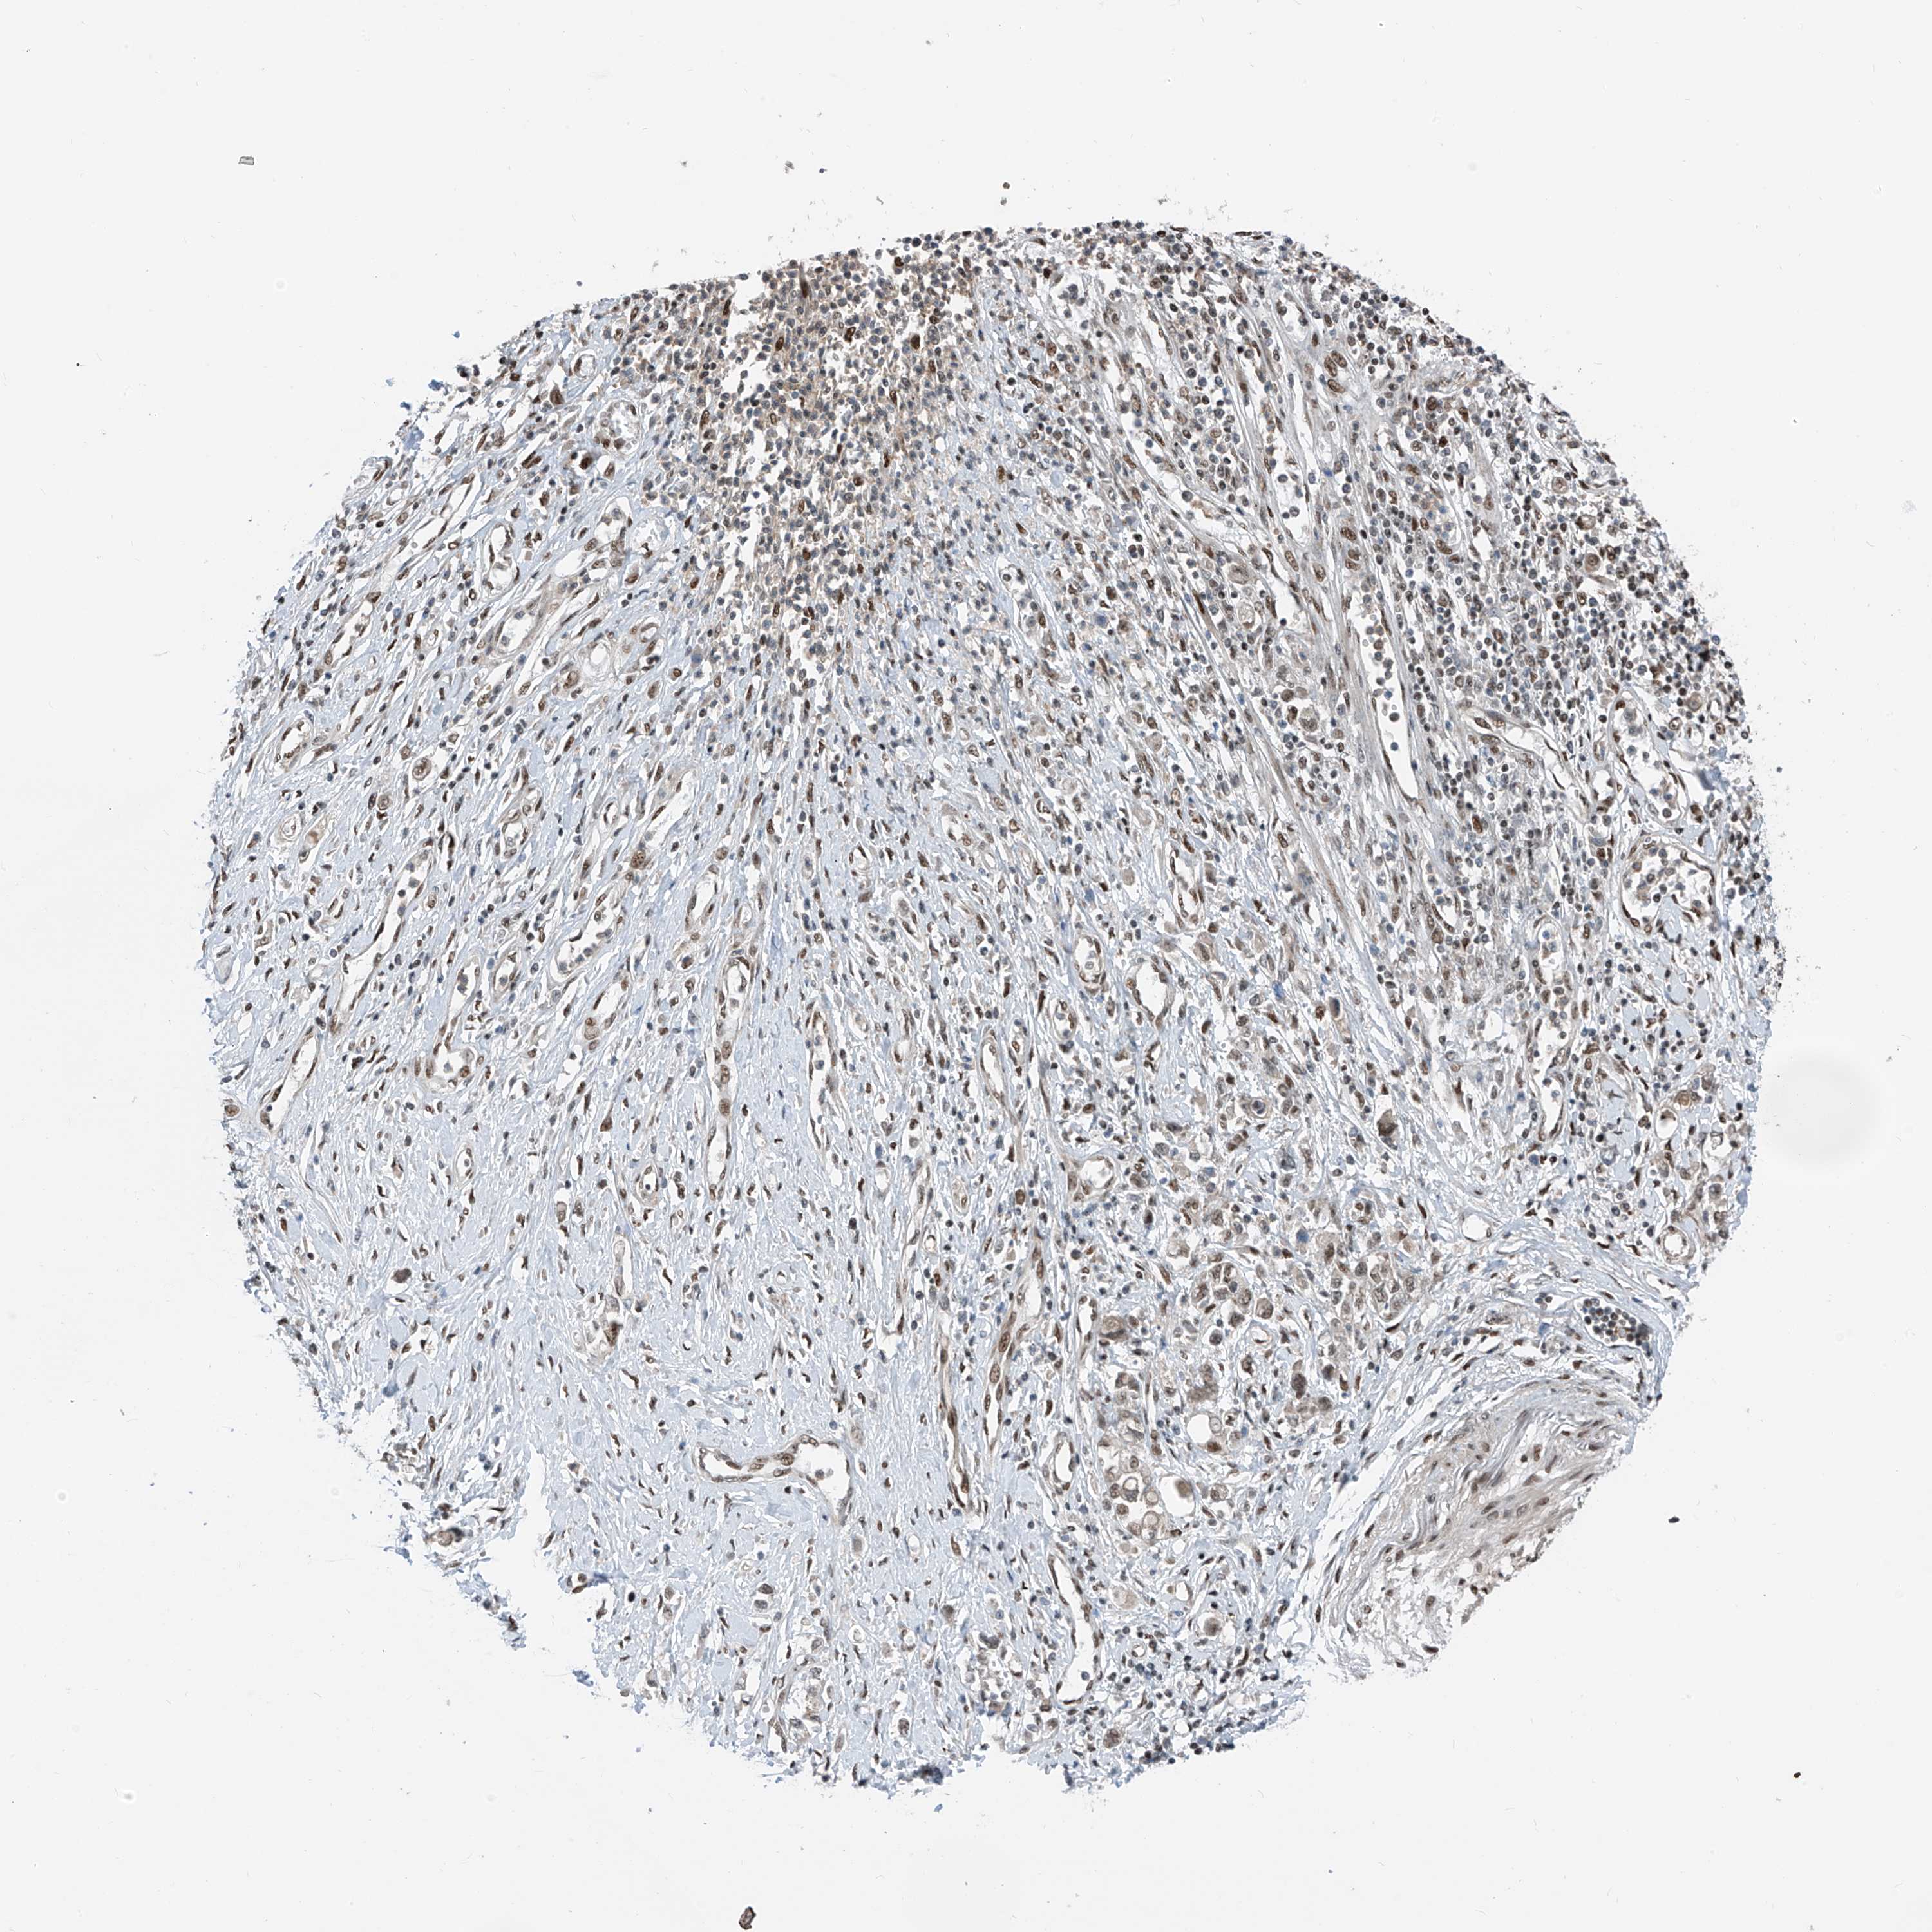

STOMACH CANCER - Protein expressioni

A mouse-over function shows sample information and annotation data. Click on an image to view it in a full screen mode. Samples can be filtered based on level of antibody staining by selecting one or several of the following categories: high, medium, low and not detected. The assay and annotation is described here.

Note that samples used for immunohistochemistry by the Human Protein Atlas do not correspond to samples in the TCGA dataset.

Antibody stainingi

Antibody staining in the annotated cell types in the current human tissue is reported as not detected, low, medium, or high, based on conventional immunohistochemistry profiling in selected tissues. This score is based on the combination of the staining intensity and fraction of stained cells.

Each image is clickable and will lead to virtual microscopy that enables deeper exploration of all samples and also displays staining intensity scores, fraction scores and subcellular localization as well as patient and tissue information for each sample.

Antibody HPA034749

Staining

High

Medium

Low

Not detected

Intensity

Strong

Moderate

Weak

Negative

Quantity

>75%

75%-25%

<25%

None

Location

Nuclear

Cytoplasmic/membranous

Cytoplasmic/membranous,nuclear

Adenocarcinoma, NOS